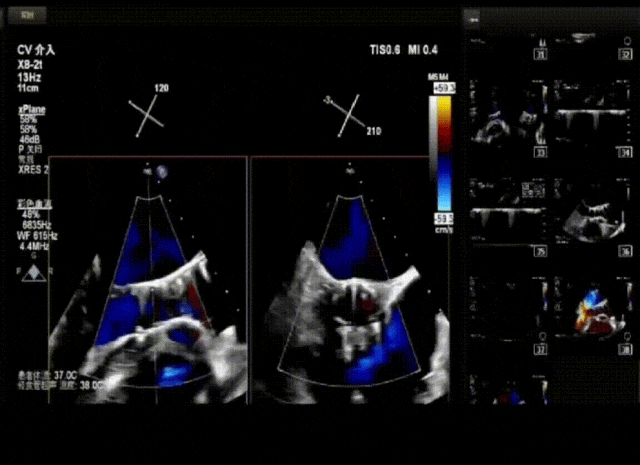

病例概览

患者病史 男性,74y, 因 “发现心脏瓣膜病 1 年,加重伴喘气半年” 入院。门诊检查显示主动脉瓣重度AS并伴轻-中度AR。患者基础疾病较多:胸腹主动脉多发穿透性溃疡、心功能III级等,手术指征明确,但风险极高。 术前CT LVOT- Annulus 倒梯形,对植入瓣膜有挤压位移风险,Annulus直径23.7mm,瓣叶增厚,钙化集中在无冠窦边缘。 左冠脉开口高度可,瓣叶不长、窦部空间较大,无冠脉风险;室间隔膜部较短,有一定PPI风险,心脏角度37.9°;心室较小,有一定循环崩溃风险,术前注意补液。 术前造影角度及入路:血管入路散在钙化、无迂曲;主动脉弓条件好、双侧股动脉直径大、右股穿刺点侧壁存在环形钙化 左右重合位:RAO 7° CAU 21° 右窦中心位:LAO2 1° CAU 1° 手术策略 20mm球囊预扩后植入AV26瓣膜,同时做好预防循环崩溃、传导阻滞的应急预案。 术中挑战 1)球囊预扩:20mm球囊预扩时无明显 “腰征”,但存在少量反流,提示瓣膜钙化与解剖结构对扩张的阻力不均 2)首次释放偏差:第一次定位释放时,瓣膜在 “开花” 过程中下滑约 3mm,工作位观察显示小弯侧瓣周漏较多(深度超过完全覆膜区),需二次调整。 3)二次精准定位:以猪尾导管为参照,将定位点调整至 “猪尾 - 2mm” 处,结合真实窦底深度(较深)重新释放,最终瓣膜位置稳定,瓣周漏显著减少。 术后即刻效果: 瓣膜形态良好,跨瓣压差从术前的 67mmHg 降至 6mmHg,且无明显瓣周漏,冠脉开口通畅; Commisural Alignment 术后即刻超声: Prostyle A®预装干瓣——助力临床最优化解决方案: √ 平衡的径向支撑力:特殊的解剖结构下位置形态良好,术后跨瓣压差大幅降低,血流动力学改善明显; √ 80%可回收设计:支持术中二次调整释放位置,保证精准释放; √ 平衡的收腰设计&Commissural Alignment设计: 为患者后期冠脉PCI保留了生命通道;